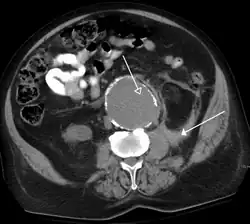

A CT scan image showing a ruptured abdominal aortic aneurysm.

Computed tomography of the abdomen and pelvis is an application of computed tomography (CT) and is a sensitive method for diagnosis of abdominal diseases. It is used frequently to determine stage of cancer and to follow progress. It is also a useful test to investigate acute abdominal pain (especially of the lower quadrants, whereas ultrasound is the preferred first line investigation for right upper quadrant pain). Renal stones, appendicitis, pancreatitis, diverticulitis, abdominal aortic aneurysm, and bowel obstruction are conditions that are readily diagnosed and assessed with CT. CT is also the first line for detecting solid organ injury after trauma.